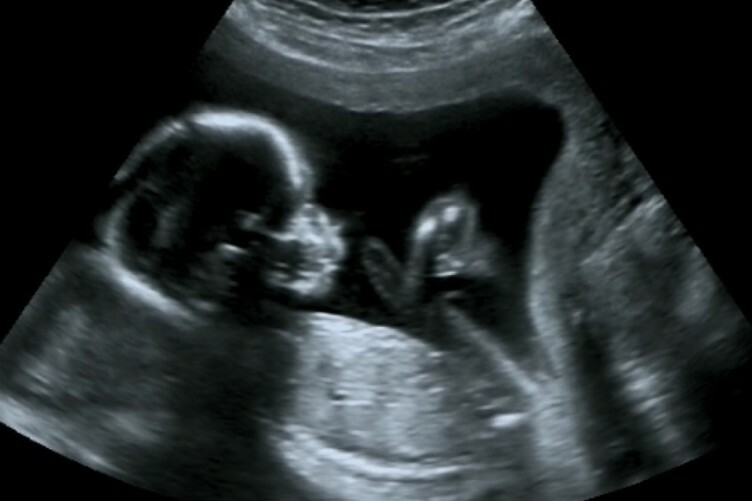

A dating scan is an ultrasound scan carried out at around 12 weeks of pregnancy, that's used to work out your due date . It's likely to be the first time you see your baby and hear their heartbeat . This scan is also used to check that your baby's development is on track and is often part of combined screening for genetic variations, such as Down's syndrome , Edwards' Syndrome and Patau's Syndrome .

If you're pregnant in England you'll be offered an ultrasound scan at around 10 to 14 weeks of pregnancy . This is called the dating scan . It's used to see how far along in your pregnancy you are and check your baby's development . The scan may also be part of a screening test for Down's syndrome . Your midwife or doctor will book you a dating scan appointment . It will usually take place at your local hospital ultrasound department .

The dating scan is usually done at some point between 8 weeks and 14 weeks pregnant .NICE recommends it's done between 10 weeks and 13 weeks . You will have had earlier appointments and may have had an early scan if you've had any concerns such as bleeding, but otherwise this is the first time you'll get to see your baby, so it's a real milestone in your pregnancy .

A dating scan at 7 weeks helps to confirm baby's presence and development, but it can also help to rule out pregnancy complications . At , the embryo matures to a foetus and individual genetics and growth factors begin to influence growth .